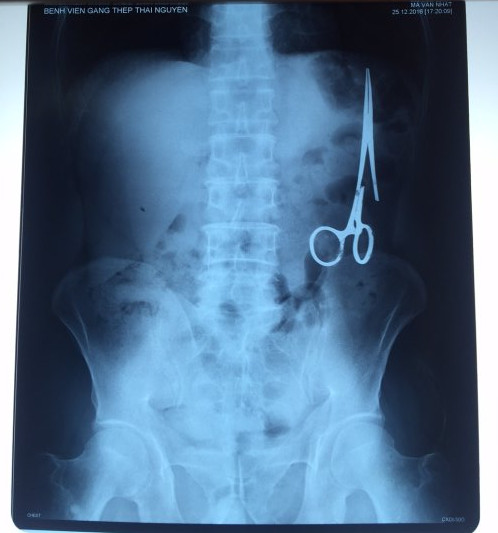

遺留在病人腹中的剪刀

醫(yī)務(wù)人員表示,這把剪刀遺留在病人腹部左側(cè),與結(jié)腸緊挨著。剪刀的把手已經(jīng)生銹,部分器官也已經(jīng)與剪刀粘連起來(lái)。但在過(guò)去多年中,M.V.N沒(méi)有任何不適感覺,也從未因?yàn)榱粼诟怪械募舻兑l(fā)的相關(guān)問(wèn)題去看過(guò)醫(yī)生。直到2016年12月,M.V.N因?yàn)樵庥隽艘粓?chǎng)車禍,才到鑄鋼醫(yī)院進(jìn)行身體檢查。

超聲波檢查顯示,M.V.N的腸子中有個(gè)奇怪物體,看起來(lái)就像醫(yī)用剪刀。M.V.N證實(shí),他曾于1998年6月份在北江省綜合醫(yī)院接受手術(shù),在此后也從未進(jìn)行過(guò)任何手術(shù)。近來(lái),他感到腹部有些疼痛,并試圖通過(guò)服用藥物治療。12月27日,M.V.N回到北江省綜合醫(yī)院再次進(jìn)行超聲波檢查,顯示其腹部的確存在怪異物體。